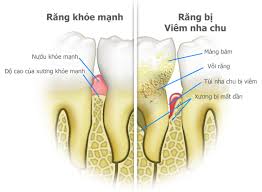

6. ĐIỀU TRỊ VIÊM NƯỚU/NHA CHU

Điều trị chuyên sâu tình trạng chảy máu chân răng, tụt lợi, hôi miệng. Giúp nướu săn chắc và giữ răng vững ổn.